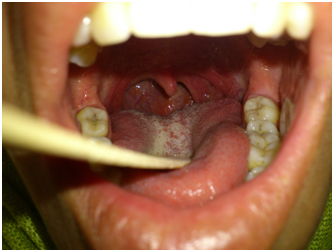

A 23-year-old female, with no relevant medical history, presented to the ENT out patient clinic for neck pain and left otalgia for the past 1 year, dysphagia for solids, snoring and dysphonia for the past 4months. Her general state was marked by significant weight loss. Clinical examination found a bulging of the left posterolateral wall of the pharynx with a regular mucosa. (Figure 1) There were no paralysis of cranial nerves nor abnormalities at otoscopy. Cervico-facial CT scan show a heterogeneous mass of the left parapharyngeal and retropharyngeal spaces of the oro and hypopharynx, measuring 6cm of diameter evoking a necrotic tumor (Figure 2). Endoscopy of the upper aero-digestive ways revealed a regular bulging with an intact mucosa of the posterolateral wall of the oro and hypopharynx with no laryngeal involvement. Deep biopsy -after incision of the mucosa- revealed a monophasic mesenchymal proliferation composed mainly of uniform spindle cells forming interlacing fascicles which was consistent with synovial sarcoma after immunohistochemistry: positive for anti-CD99, anti-bcl and Anti-vimentin, negative for anti-PS 100, anti-cytokeratin, anti-desmin and anti-CD34. Extension work up including chest CT scan, abdominal ultrasonography and bone scintigraphy have not found any distant metastases. The patient underwent a chemotherapy pending for radiotherapy according to the multidisciplinary ENT-Oncology staff decision. After the 2nd cure of chemotherapy, the patient presented respiratory symptoms that prompted a chest CT scan showing multiple pulmonary metastases. Patient then underwent a palliative chemotherapy.

Figure 1 A bulging of the left posterolateral wall of the pharynx with a regular mucosa.